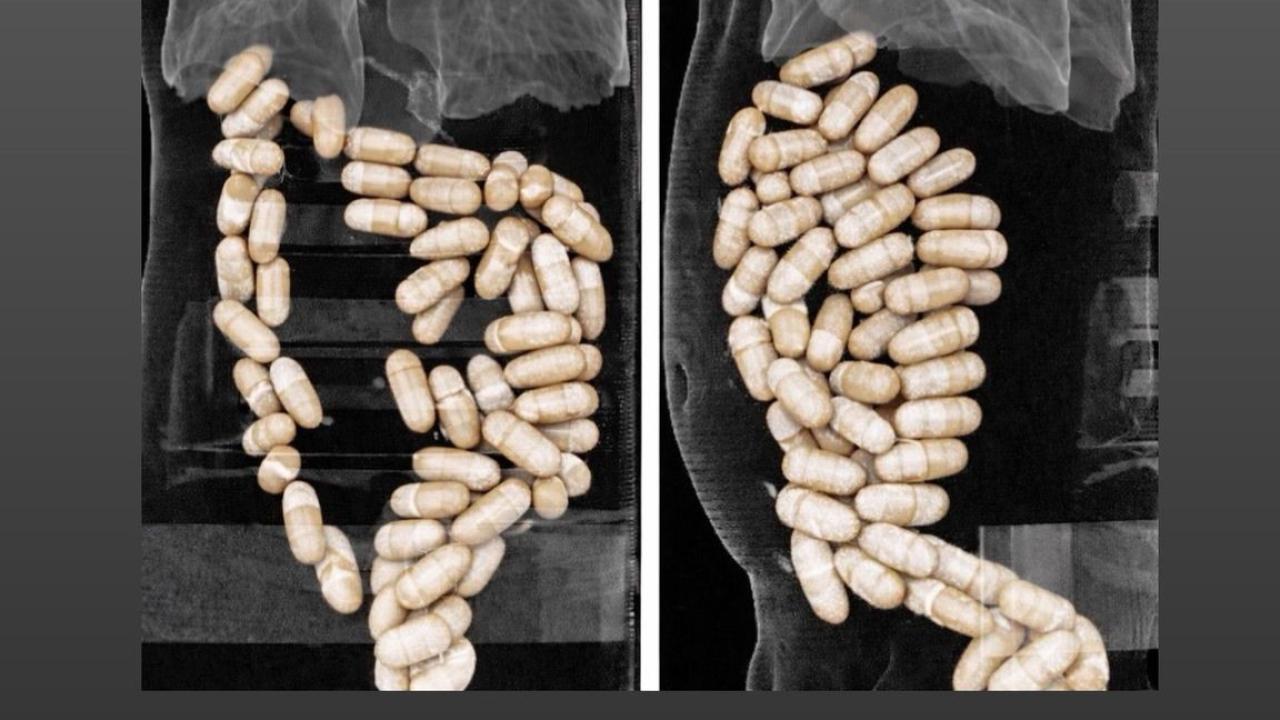

Gerçekleştirilen tıbbi müdahaleyle şüphelilerin midesinden 127 kapsül halinde yutulmuş toplam 1 kilo 304 gram eroin çıkarıldı. Operasyon kapsamında gözaltına alınan E.E. ve N.M. isimli şüpheliler, emniyetteki işlemlerinin ardından mahkemece tutuklanarak cezaevine gönderildi.